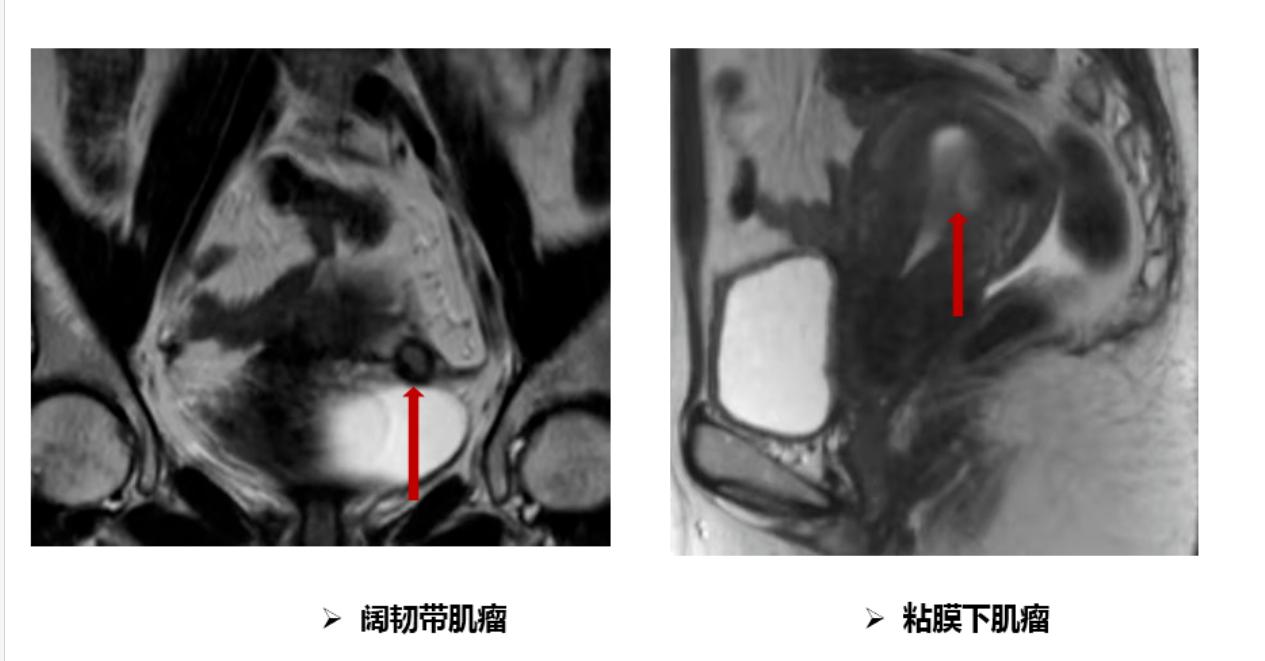

平素月经规律,5-6天/29天,量中,痛经(-),LMP:2021-10-24。3年前体检查妇科彩超提示子宫肌瘤,直径约2cm。无相关不适症状,建议定期复查。期间不定期复查彩超提示子宫肌瘤逐渐增大。10个月前无明显诱因出现经量增多,约为原来的2-3倍,伴血块,经期延长,最长达14天,月经周期未见明显改变,口服药物(具体不详)治疗未见好转。为明确诊治就诊我院门诊,查妇科彩超提示:子宫后壁可见6.99x5.35cm的低回声团,向前压迫子宫内膜,宫腔可见深度约0.55cm的无回声区,宫颈形态规则,内未见异常回声,子宫左侧可见1.75x1.21cm的低回声团,与子宫关系密切。建议住院手术治疗。

入院后在基础麻醉下行宫腔镜检查术。术中探查:探宫腔深8cm,宫腔形态基本规则,子宫后壁可见一直径约1.5cm肌瘤凸向宫腔,双侧输卵管开口可见。